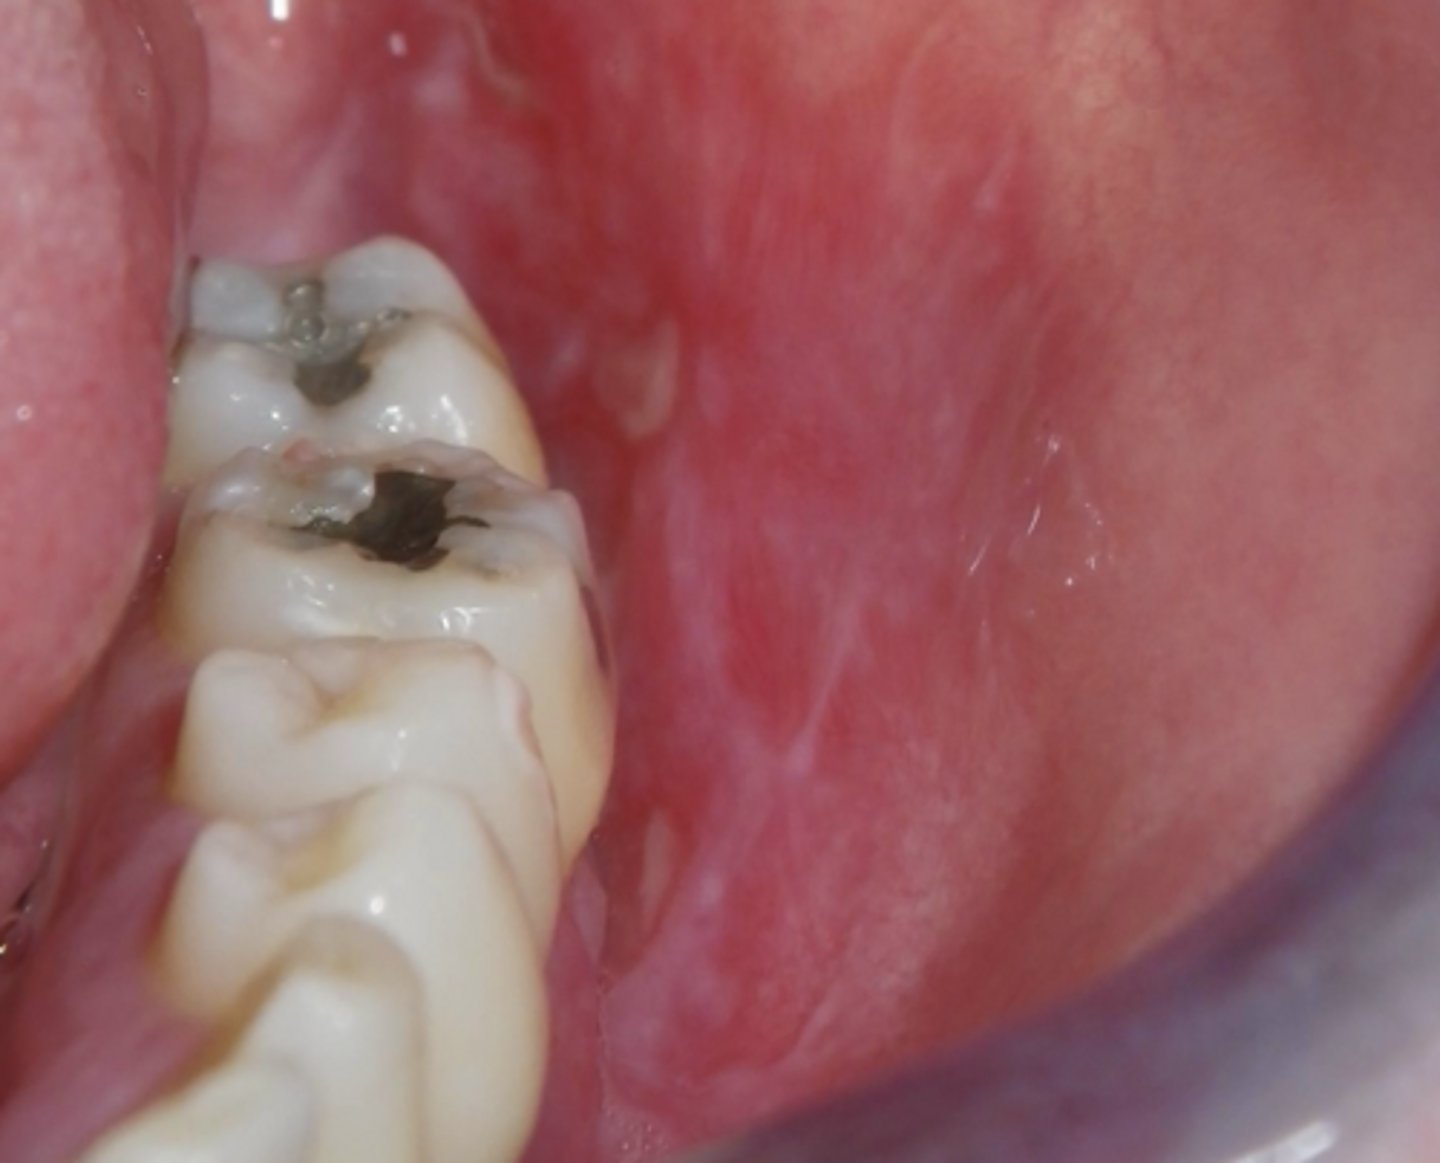

lichen planus (ulcerative)

What type of lichen planus?

- Least common form

- Usually symptomatic

- Ulcers w/ striae + erythema

- May cause desquamative gingivitis

- Must be distinguished from mucous membrane pemphigoid or pemphigus